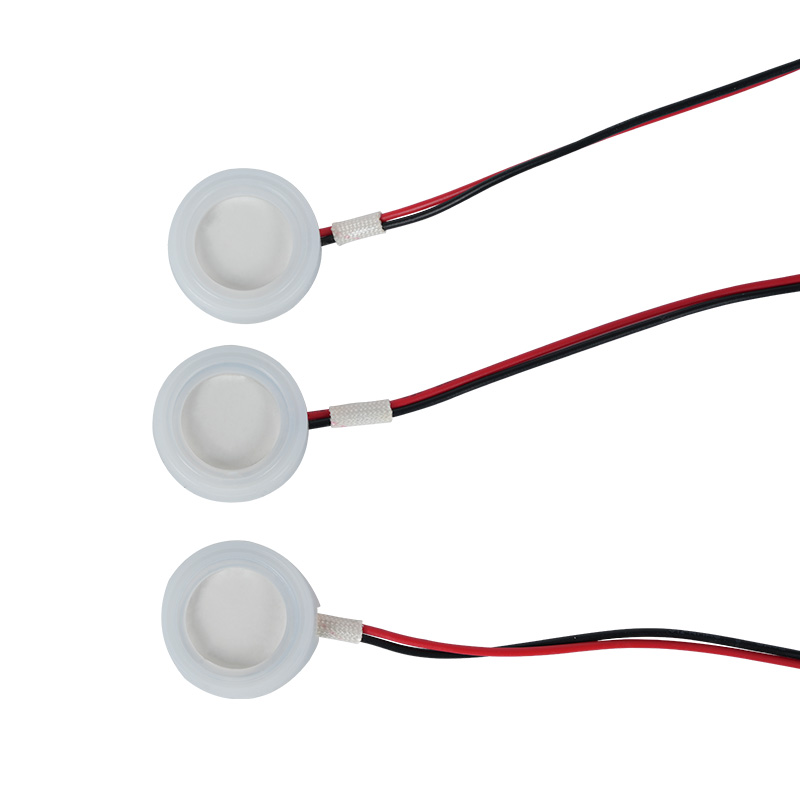

Polyimid (Polyimid) označovaný jako PI, je nejlepší komplexní výkon organických polymerních materiálů, má vynikající chemickou stabilitu a může odolat korozi různých léků, aby bylo zajištěno dlouhodobé používání atomizovaných tablet. Kromě toho je vynikající tepelná stabilita polymerního PI filmu, s dlouhodobým používáním teplotního rozsahu -200 ~ 300 ° C, vysokou izolací, ochranou životního prostředí a netoxicitou, jako speciální inženýrský materiál, široce používaný v letecké mikroelektronice, separační membrány z nano-kapalných krystalů a další obory, byl v 21. století zahrnut zeměmi jednoho z nejslibnějších inženýrských materiálů. deformované v procesu vysokoteplotní dezinfekce, aby bylo zajištěno opětovné použití! Pro sex a bezpečnost používáme laserovou technologii pro laserovou perforaci, PI film implantovaný mezi nerezovou ocel a piezoelektrickou fólii, použití piezoelektrické keramické ultrazvukové technologie tak, aby se atomizované kapičky přes PI film rozptýlily do atomizace 3 ~ 4 μm částic pro inhalaci lékařskou nebulizací, bezpečnost většiny uživatelů miluje, vyrobeno z hlavního nebulizéru s PI výhoda non-ucpání, vnitřní stěna otvoru v hladké a zaoblené, žádné zbytky kapaliny, atomizace jemné a stabilní. Atomizace je jemná a stabilní. Tablety PI filmového nebulizátoru mohou účinně zabránit zbytkům léků, snížit riziko křížové kontaminace. V praktické aplikaci se také promítly charakteristiky nízké spotřeby energie polymerních PI membránových nebulizačních tablet, shrnuto, polymerové PI membránové nebulizační tablety se se svým vynikajícím výkonem a konstrukčními výhodami staly nepostradatelnou součástí oblasti lékařské nebulizační terapie.